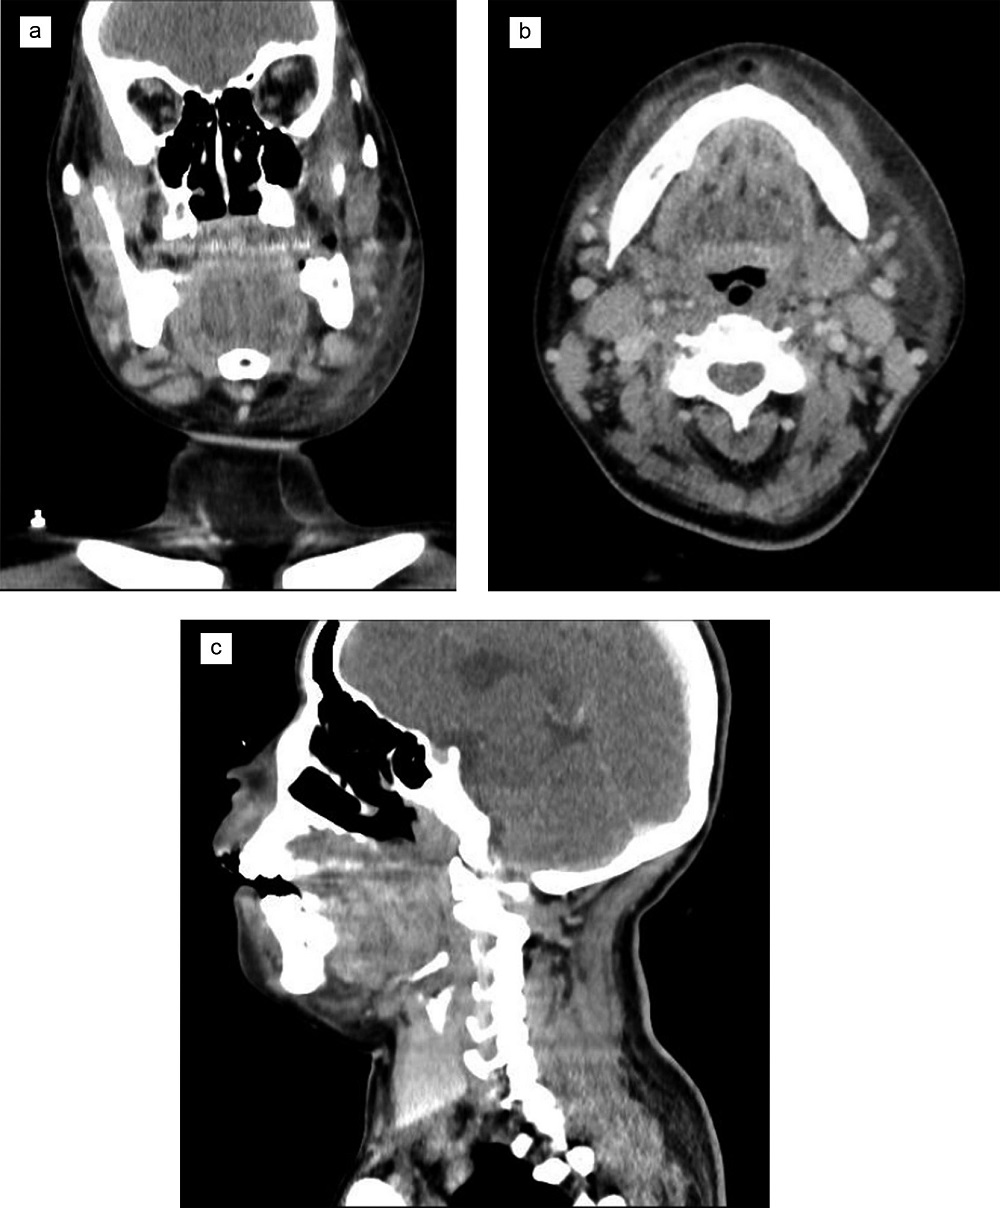

Se le realiza una tomografía espiral multicorte (TEM) de cuello y macizo facial con contraste, apreciándose un aumento de volumen de las partes blandas del espacio submandibular izquierdo, edema y colección adyacente en cuerpo mandibular izquierdo con un volumen aproximado de 20 cc, que muestra realce periférico tras el contraste, extendiéndose al espacio masticador, que da la impresión diagnóstica de colección abscedada en región submandibular izquierda (figura 2).